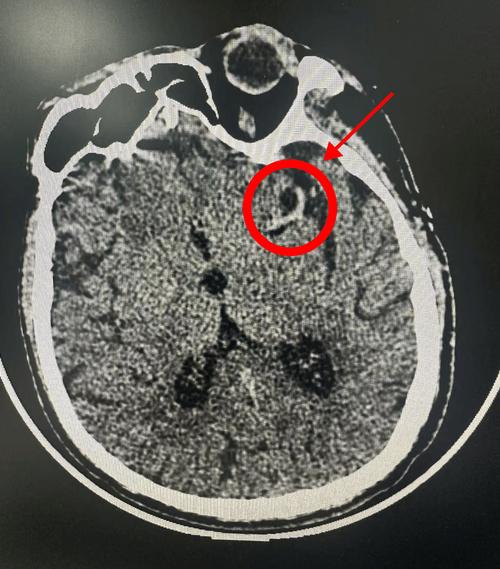

- 豆状核边缘模糊:这是一个非常经典的早期征象,正常情况下,大脑深部的“豆状核”结构边界非常清晰,当供应它的血管发生缺血时,这个边界会变得模糊不清。

- 右侧基底节区可见一小片状稍低密度影,边界欠清,范围约Xcm×Ycm,符合急性脑梗死改变。 (或:右侧额叶皮质下可见小片状低密度灶...)

诊断意见: 右侧基底节区急性脑梗死(建议结合临床及MRI进一步明确)。

- “右侧基底节区...低密度影”:发现了病灶,位置在右侧基底节区,这里是常见的脑梗好发部位(供应血管是大脑中动脉的深穿支)。